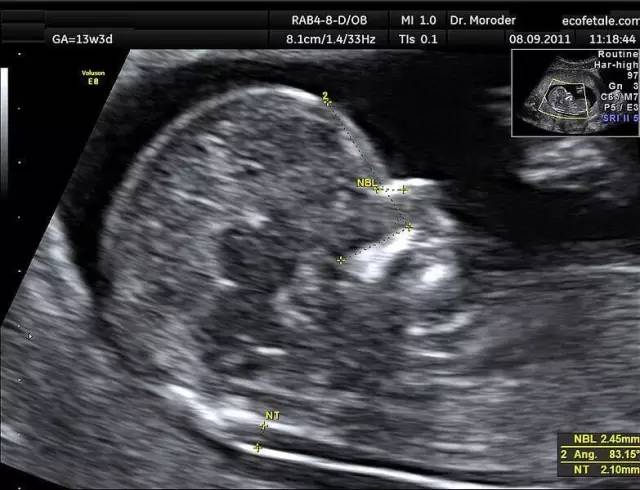

(NT超声图)

“NT”是“颈项透明层”的英文简写,是指流动在颈项后面的一层半透明蛋白膜,胎宝宝在10~13周时,可用B超来成像,通常说为B超NT。

正常胎儿的NT厚度应该在3.0mm以内。NT超过正常值,越厚,说明唐氏儿风险就越高。

B超测量NF,是从颈椎水平矢状切面皮肤至皮下软组织之间的最大厚度。正常胎儿NF厚度范围为6.0mm以内。超过后,NF越厚,唐氏儿风险就越高。